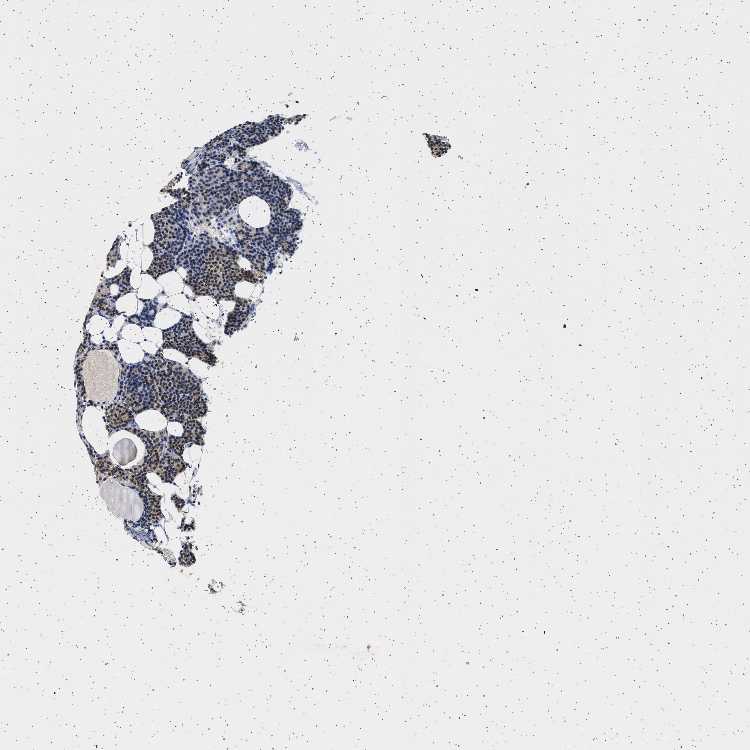

PARATHYROID GLAND - Antibody stainingi

Antibody staining in the annotated cell types in the current human tissue is reported as not detected, low, medium, or high, based on conventional immunohistochemistry profiling in selected tissues. This score is based on the combination of the staining intensity and fraction of stained cells.

Each image is clickable and will lead to virtual microscopy that enables deeper exploration of all samples and also displays staining intensity scores, fraction scores and subcellular localization as well as patient and tissue information for each sample.

Antibody HPA018096

Glandular cells Medium